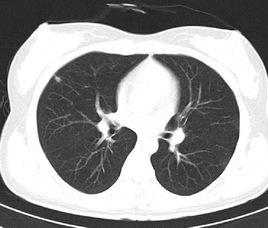

2.肺臟:對周圍型肺癌的早期診斷有價值;發現主支氣管、肺葉支氣管及肺段支氣管狹窄或截斷時,對診斷中央型肺癌有幫助;高解析度CT(HRCT)可能顯示胸片不能顯示的瀰漫性間質性病變,有助於早期診斷和鑑別診斷;還可發現胸片上不能顯示的肺大泡、支氣管擴張、較小的肺結核空洞等。

6.CT由於是斷層掃描,並且具有比胸片高10倍的密度解析度,能夠輕易發現直徑小於2mm的微小結節。